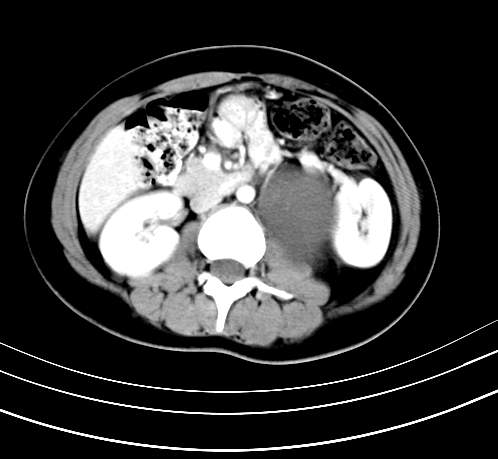

标题: CT23915:女 20岁 全身长疙瘩三年 今日多体位查 看看吧 [打印本页]

标题: CT23915:女 20岁 全身长疙瘩三年 今日多体位查 看看吧

静脉期

延时5分钟